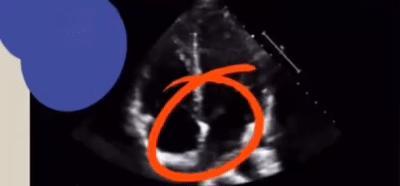

房间隔膨出瘤

ASA并非真正的肿瘤,而是由于先天性房间隔发育薄弱,在心脏负荷压力的作用下局部向低压侧心房膨隆而形成的气球样或囊袋样膨出。这种膨出还能够随心动周期的变化而在两房之间来回摆动。在临床中,ASA属于比较少见的先天性心脏病,在儿童中的发病率约0.9% 1.7%,在成人中的发病率约1.9% 2.4%,女性发病率高于男性。

长期以来,ASA的诊断主要依赖于心脏超声检查。然而,随着医学影像技术的进步,诊断方法也在不断演变。最初,传统的经胸超声心动图(TTE)是主要的诊断工具。但研究发现,经食管超声心动图(TEE)和右心对比增强经胸超声心动图(cTTE)能够更准确地检测到ASA及其相关并发症。例如,一项研究显示,TEE检测卵圆孔未闭(PFO)分流的阳性率显著高于TTE(42.72% vs 18.84%,P<0.001)。cTTE的检测率更是显著高于TTE和TEE(69.56% vs 18.84%和42.72%,P<0.001)。

ASA的诊断标准也逐渐明确。一般认为,瘤体基底部宽度≥1.5 cm,瘤深或最大活动幅度≥1.1-1.5 cm即可诊断。然而,由于ASA的诊断标准尚未达成共识,其诊断仍存在一定的挑战。